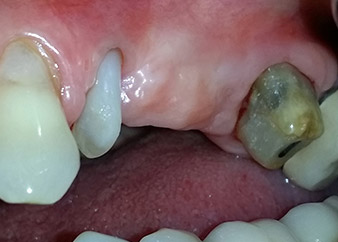

Una paziente donna di 58 anni lamentava dolore e aumentata mobilità del dente di appoggio del ponte 24. Era presente infiammazione periodontale con tasche di profondità di 7 mm a livello mesiobuccale e di più di 12 mm a livello distale, nonché coinvolgimento di terzo grado della forcazione. Inoltre, la radiografia rivelava una lesione periodontale estensiva attorno alla regione apicale del dente pretrattato 24 (in altro luogo) a livello endodontico (Fig. 1).

Un anno più tardi, sono stati estratti i denti 25 e 26 in seguito a trauma e per motivi endoperiodontali, prima del posizionamento del ponte. Era stata diagnosticata una lesione endoperiodontale combinata in corrispondenza del dente 24, di eziologia incerta. La paziente desiderava conservare i denti 24 e 27 di appoggio al ponte e non accettava una protesi rimovibile finale, o temporanea. Si è pertanto deciso di fare il possibile per conservare entrambi i denti, nonostante la prognosi negativa basata sugli esiti clinici e radiologici.

Un mese più tardi, nel giorno programmato per l'intervento, il dolore e l'infiammazione in corrispondenza del dente 24 erano minimi, ma era ancora presente mobilità di classe 2 secondo Miller. Dopo l'apertura dei lembi e la pulizia del tessuto periapicale e periradicolare infetto, l'estensione della mancanza ossea si è resa evidente (Figg. 2 e 3).

Tutto il tessuto osseo vestibolare e distale era mancante in corrispondenza della radice buccale. La possibilità di attacco era essenzialmente ristretta alla radice palatale, evidenziando la prognosi negativa preliminare. Anche il dente 27 mostrava un punto di attacco orizzontale ridotto e una rarefazione apicale minima (cfr. Fig. 1), senza sintomi clinici.